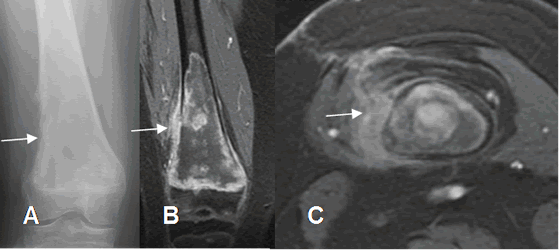

Fig 71 B. Osteosarcoma.

A: Rx AP, B: RM coronal en STIR y C: RM axial en STIR. Lesión permeativa en el fémur distal, acompañada por masa de tejidos blandos, que corresponde a osteosarcoma.